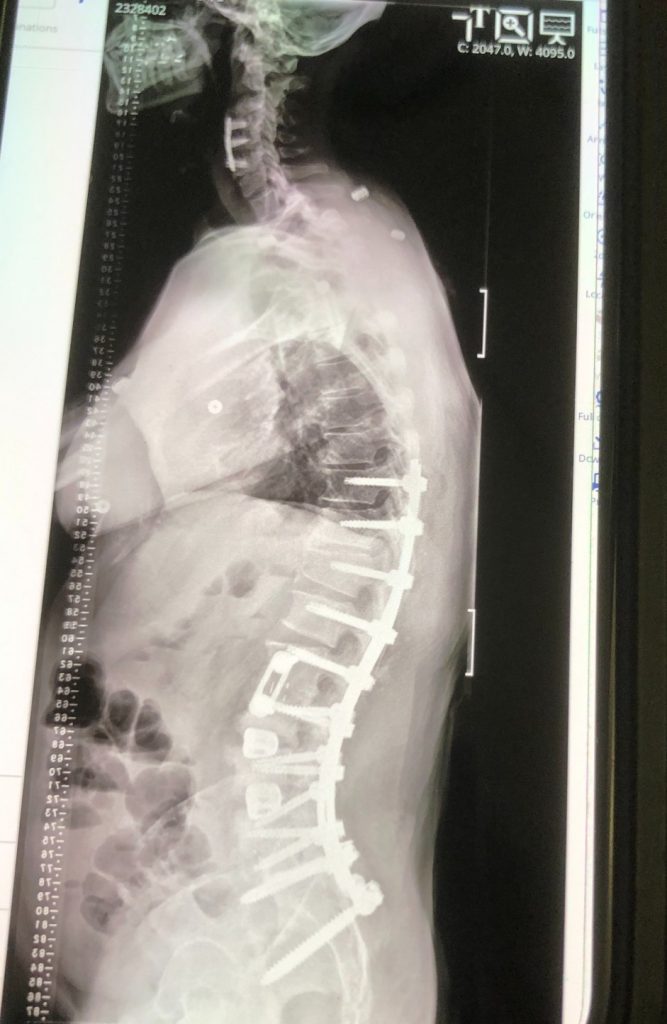

Disc Replacement Surgery